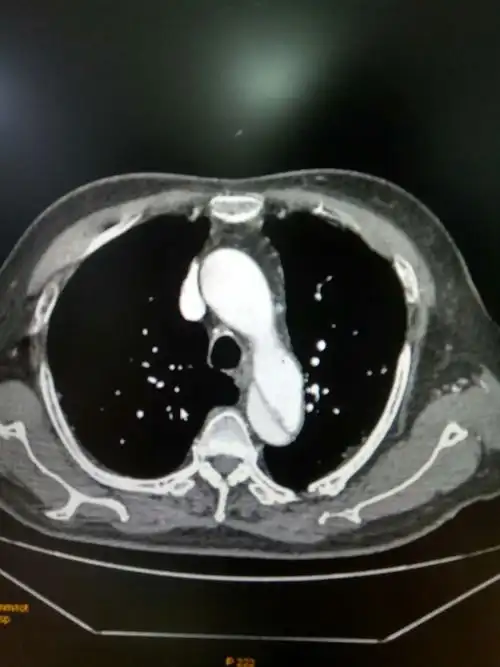

非心源性胸痛之主动脉夹层介入治疗病例汇报